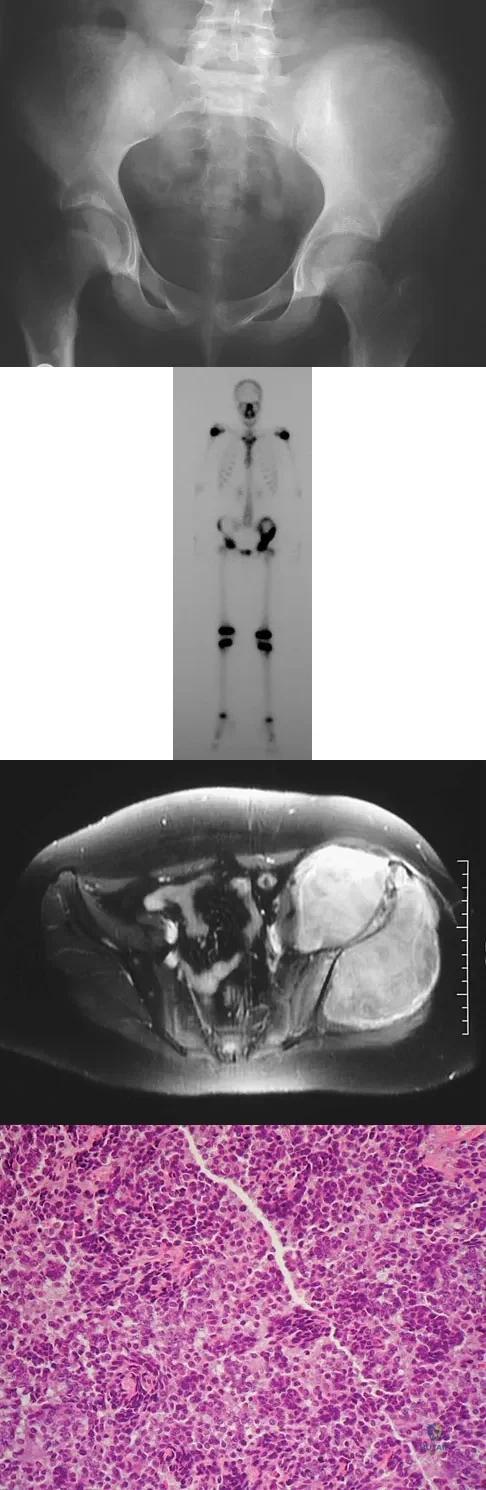

A 45-year-old man has had left thigh pain for the past 4 months. An AP radiograph, bone scan, MRI scans, and biopsy specimens are shown in Figures 6a through 6f. What is the most appropriate treatment?

Explanation